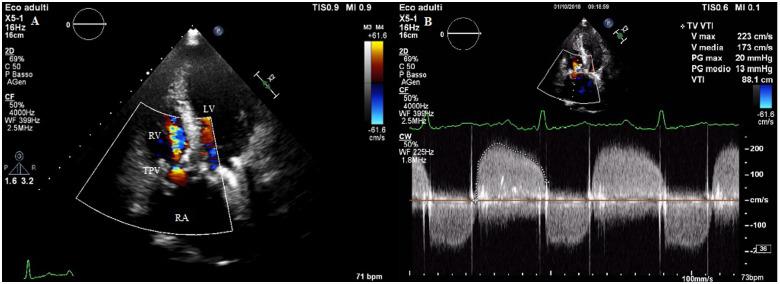

A 22-year-old woman from sub-Saharan Africa known for a triple valve replacement was hospitalized for dyspnoea and haemoptysis. A careful clinical evaluation excluded the most common causes of haemoptysis. Transthoracic echocardiogram showed normal biventricular function, normally functioning mechanical prosthetic aortic and mitral valves, and the biological tricuspid prosthesis showed an increased transvalvular gradient. Contrast chest computed tomography scan excluded pulmonary embolism and mechanical valve obstruction, but revealed marked systemic venous hypertension. Right heart catheterization confirmed increased right heart pressures and severe bioprosthetic tricuspid valve stenosis. The patient underwent a successful percutaneous tricuspid valve-in-valve replacement, with complete resolution of symptoms.

一名来自撒哈拉以南非洲的22岁女性,因三尖瓣置换术而闻名,因呼吸困难和咯血住院。仔细的临床评估排除了咯血的最常见病因。经胸超声心动图显示双心室功能正常,机械人工主动脉瓣和二尖瓣功能正常,生物三尖瓣人工瓣膜显示跨瓣压差增加。胸部增强计算机断层扫描排除了肺栓塞和机械瓣膜梗阻,但显示有明显的体静脉高压。右心导管检查证实右心压力升高和严重的生物瓣三尖瓣狭窄。患者接受了成功的经皮三尖瓣瓣中瓣置换术,症状完全缓解。